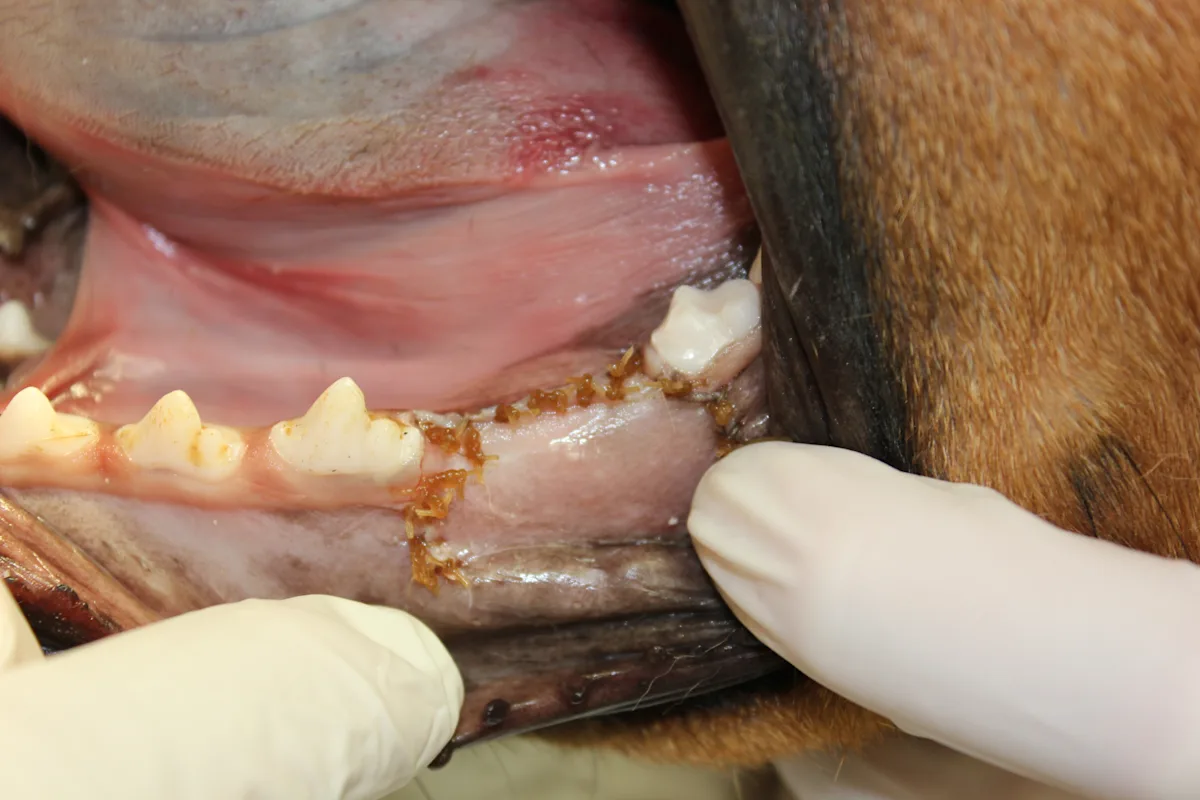

Step 12

Release tension on the mucoperiosteal flap by applying light pressure on a #15 scalpel blade while incising the periosteum. Make the incision across the base of the flap.

To decrease the likelihood of cutting through the mucoperiosteal flap, use a new scalpel blade and apply very light pressure.

Step 13

Gently place the mucoperiosteal flap over the alveolus. The flap should completely cover the alveoli without tension. Damaged tissue may be trimmed from the margins with 6-inch Metzenbaum scissors (straight).